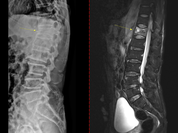

인제대학교 부산백병원(원장 양재욱)이 최신형 컴퓨터단층촬영장치(CT)와 자기공명영상장치(MRI)를 도입해 심뇌혈관 및 응급질환 진단 역량을 한층 강화했다. 특히 CT는 응급의료센터에 설치돼 뇌졸중과 심근경색 등 ‘골든타임’이 중요한 심뇌혈관 환자의 신속한 진단에 활용한다. 이는 최근 보건복지부가 지정한 ‘지역 심뇌혈관질환센터’ 운영에 더해 지역 내 심뇌혈관 응급의료 체계를 더욱 강화할 전망이다. 부산백병원은 3월부터 두 장비 모두 본격 운영에 들어갔다. CT장비 ‘Revolution APEX Elite’는 초고속 회전 기술과 넓은 검출 범위를 갖춘 최첨단 장비로, 기존 CT보다 빠르고 정밀한 영상 촬영이 가능하다. 0.23초의 초고속 회전 속도와 160mm의 넓은 촬영 범위를 갖춰 매우 짧은 시간 안에 심장과 뇌혈관을 정밀하게 촬영할 수 있는 것이 특징이다. 응급 뇌졸중 환자의 뇌혈류 상태를 확인하는 뇌관류(Perfusion) 검사를 빠르게 시행할 수 있으며, 심전도 장치(ECG) 부착 없이도 심장 촬영이 가능한 기술이 적용돼 심근경색과 같은 중증·응급 검사에서 신속한 검사가 가능하다. 함께 도입된 MRI장비 ‘SIGNA Premier 3.0T’는 딥러닝 기